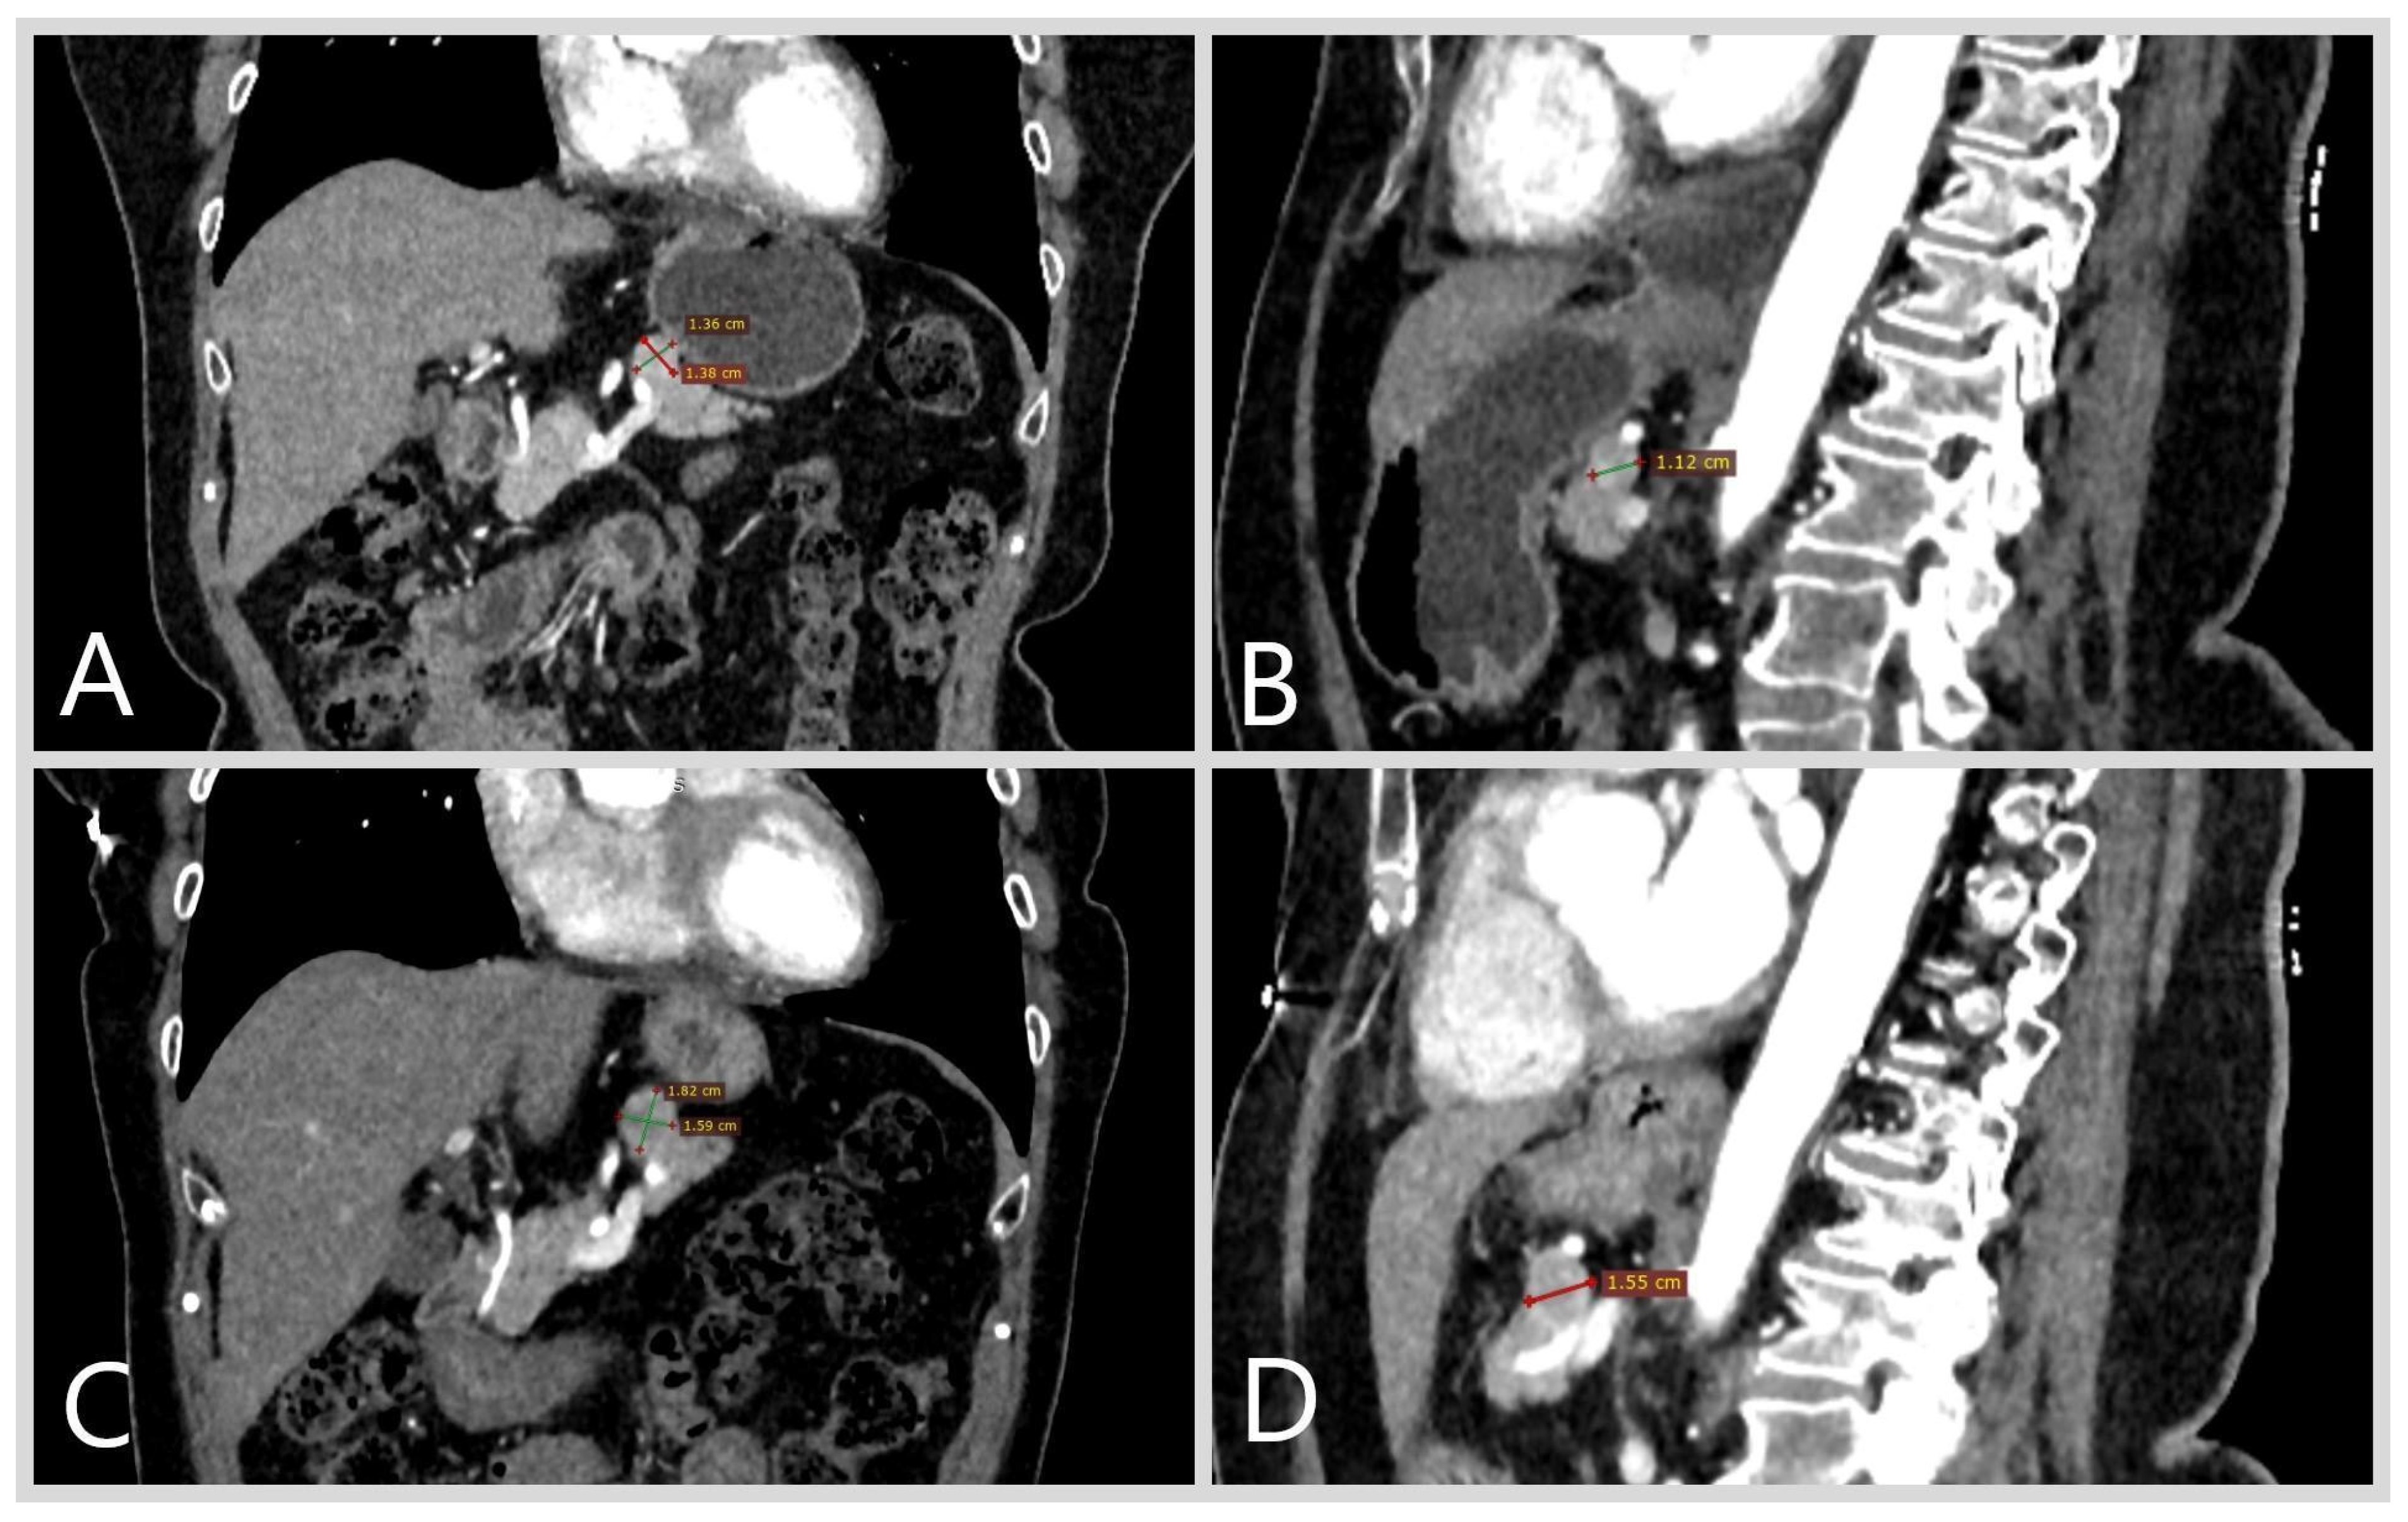

2. Case Report